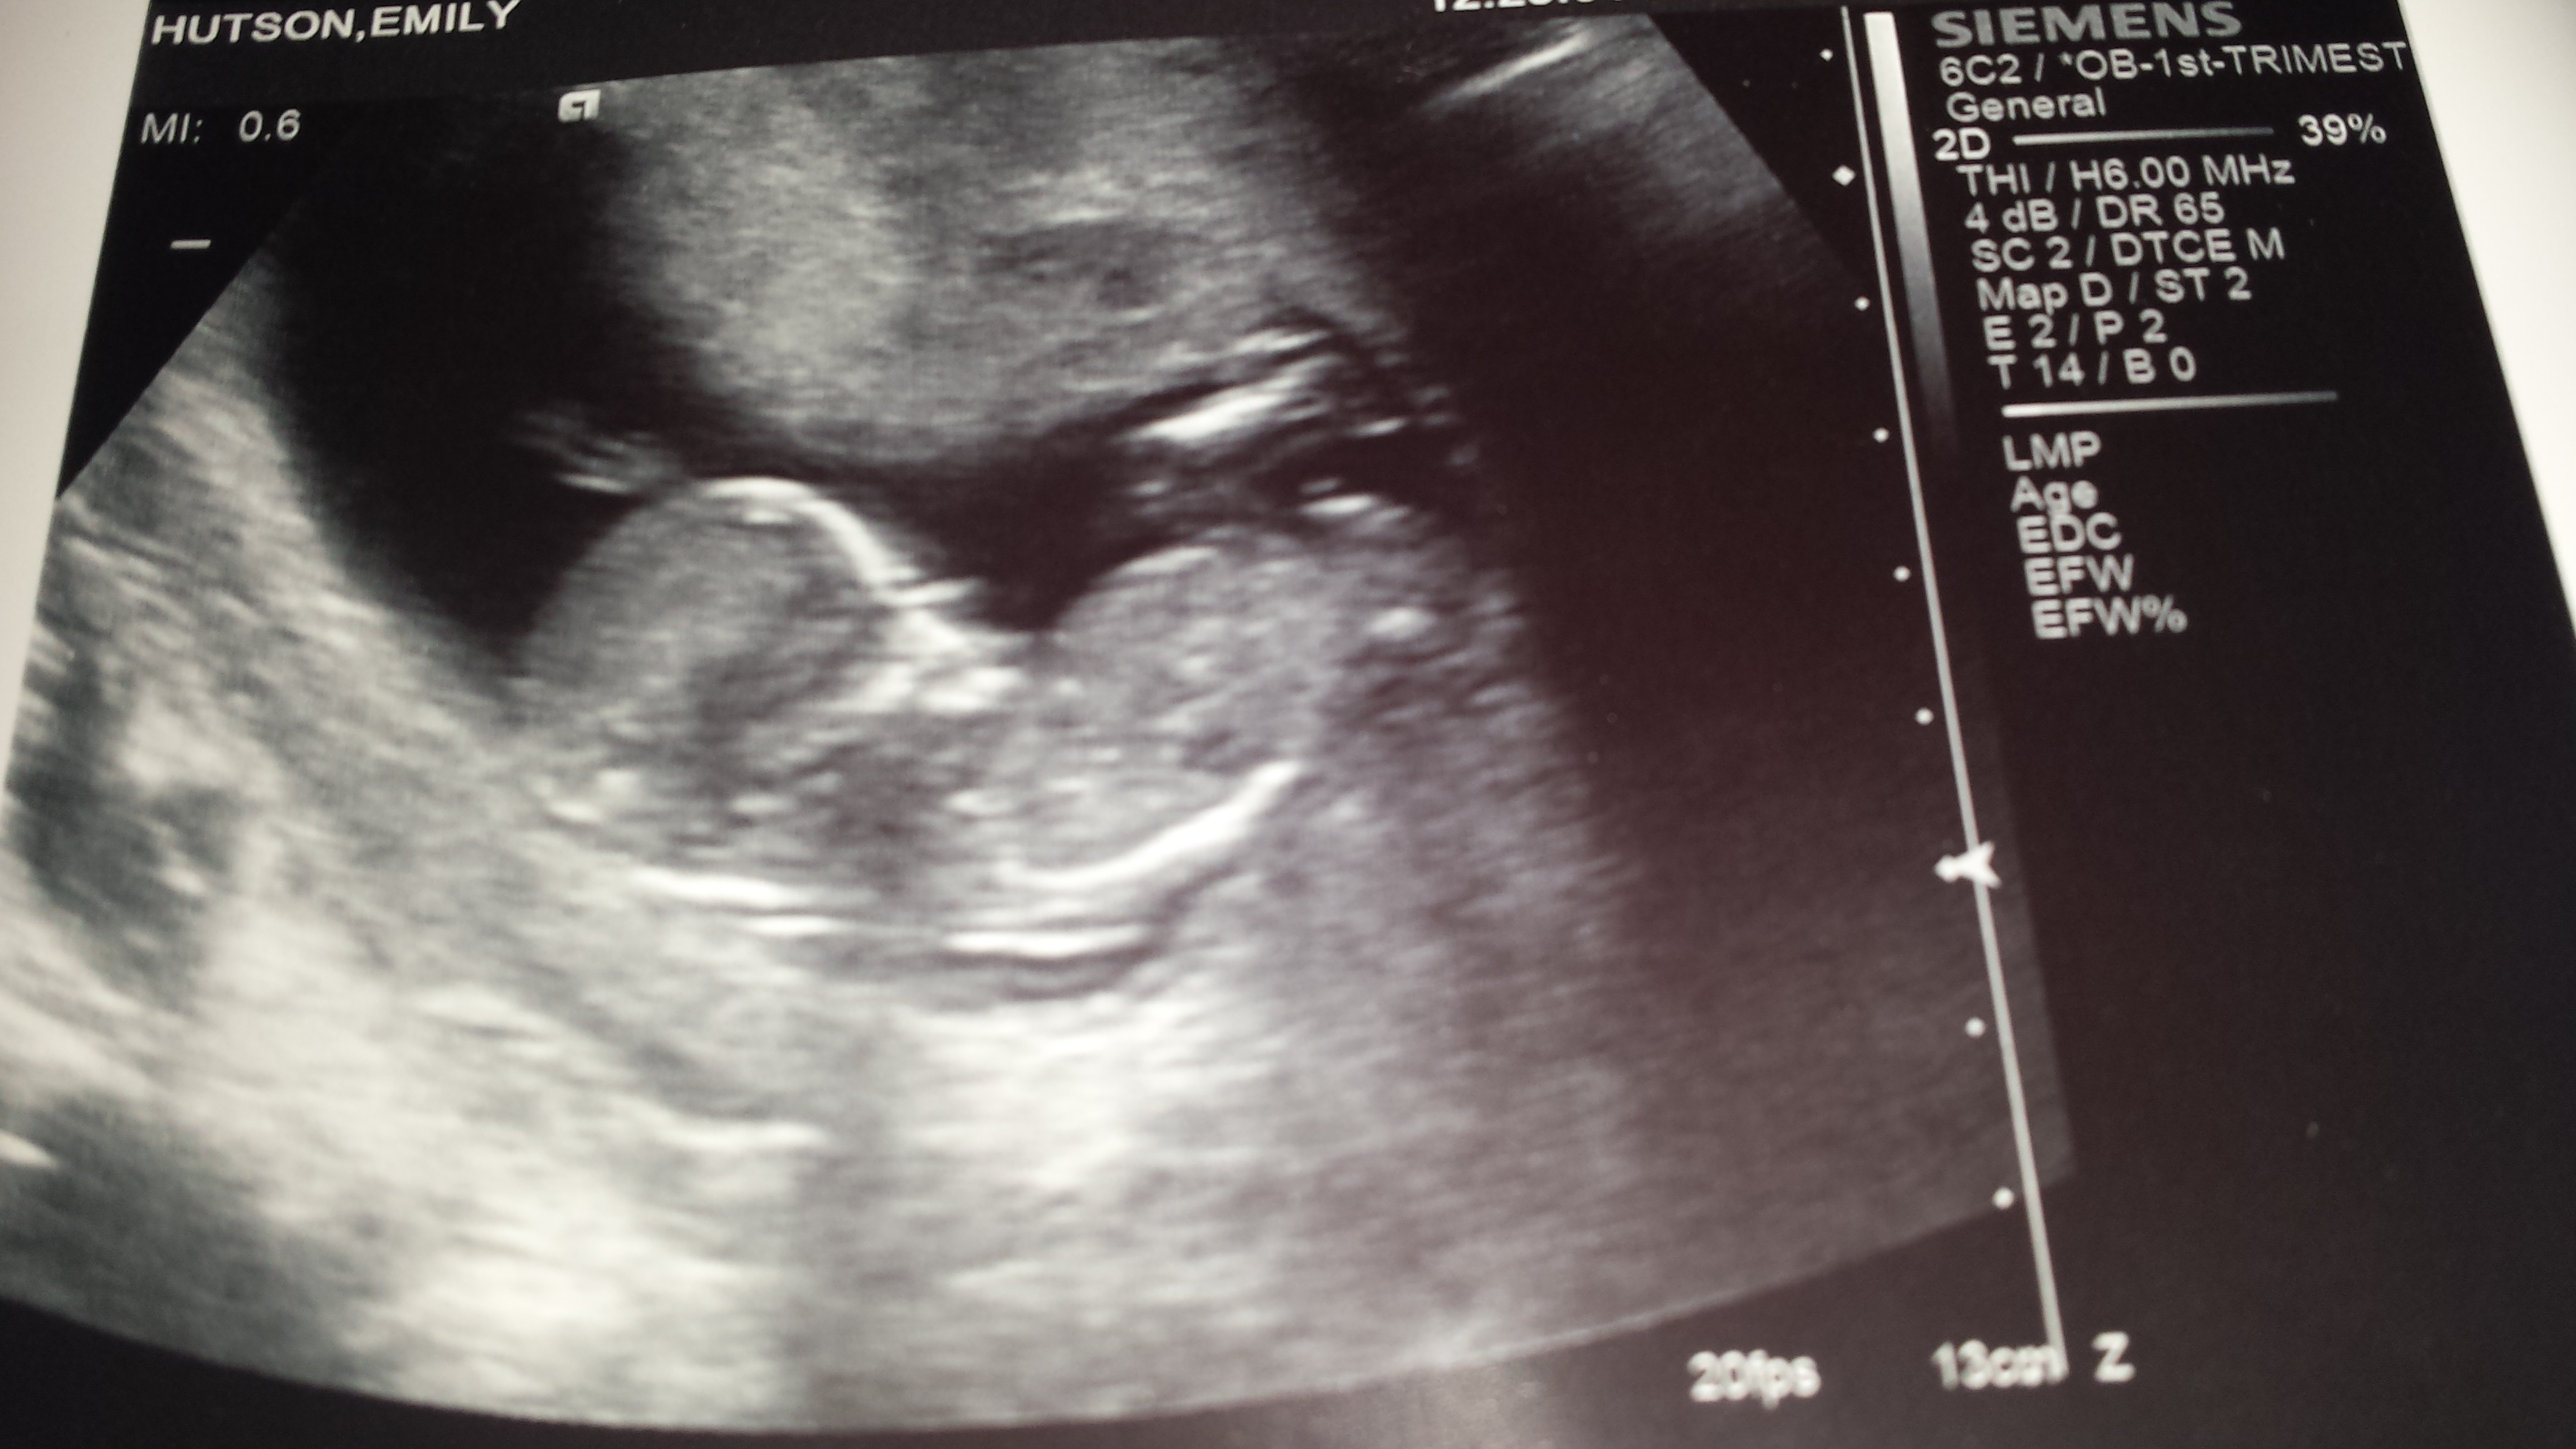

12 weeks 2 days...3 boys - could this be our girl?

I had my 12 week scan today :-) A very lazy little bean who didn't want to cooperate with the camera lol....but please, if any of you ladies could take a guess at what we are having I would really appreciate it! We already have 3 beautiful boys and of course just want a healthy baby, but a bit of femininity in my house would put the biggest smile on my face right now :-) Thanks in advance xxx